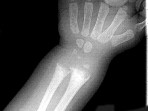

- 单项选择题男,2岁, 关节肿胀,结合图像, 最可能的诊断是 ( )

A、肾性骨病

B、黏多糖贮积症

C、维生素D缺乏症

D、维生素C缺乏症

E、维生素D过多症